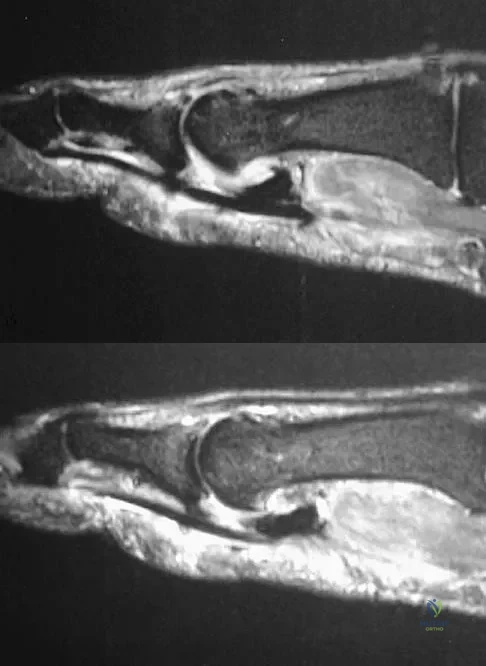

A 19-year-old college student reports a 1-week history of wrist pain following an intramural rugby match. A PA radiograph is shown in Figure 6. He denies any prior wrist injury. What is the best course of action?

Explanation